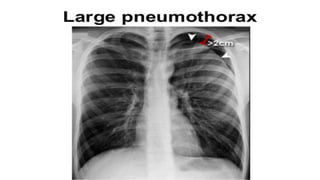

Pneumothorax

Erect

Small

Apical lucency

Visceral Line

Large

>2 cm